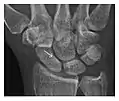

High-energy trauma fractures

Occult osseous injuries may result from a direct blow to the bone by compressive forces of adjacent bones against one another or by traction forces during an avulsion injury. Lesions in the tibial plateau, hip, ankle, and wrist are often missed. In a tibial plateau fracture, any disruption of the posterior and anterior cortical rims of the plateau should be sought. Impaction of subchondral bone will appear as an increased sclerosis of the subchondral bone (Figure 1). In the hip, posterior acetabular fractures also present subtle radiographic findings. The acetabular lines should then be carefully examined keeping in mind that the posterior rim, which is harder to see on X-rays, is more frequently fractured than the anterior rim (Figure 2). In the wrist, detection of carpal bone fractures is often challenging, with up to 18% of scaphoid fractures radiographically occult. Carpal fractures, especially the scaphoid, are associated with the risk of avascular necrosis. In apparently normal wrist radiographs from symptomatic patients, if there is history of a fall on an outstretched hand with pain in the anatomic snuffbox, suggesting scaphoid injury, the initial examination with posteroanterior, lateral, and pronation oblique views must be complemented by other specific views such as supination oblique and the "scaphoid" view A careful examination of cortices for evidence of discontinuity or offset and cancellous bone for lucency is necessary (Figure 3).[1]

a

b

c

Figure 3: A 26-year-old man presenting with wrist pain after being assaulted. (a) Initial anteroposterior radiograph shows a subtle linear lucency within the scaphoid extending to the scaphocapitate articular surface that was overlooked (arrow). (b) Initial "scaphoid" view was negative. (c) Followup anteroposterior radiographs, 12 days later, shows obvious scaphoid fracture (arrows).[1]